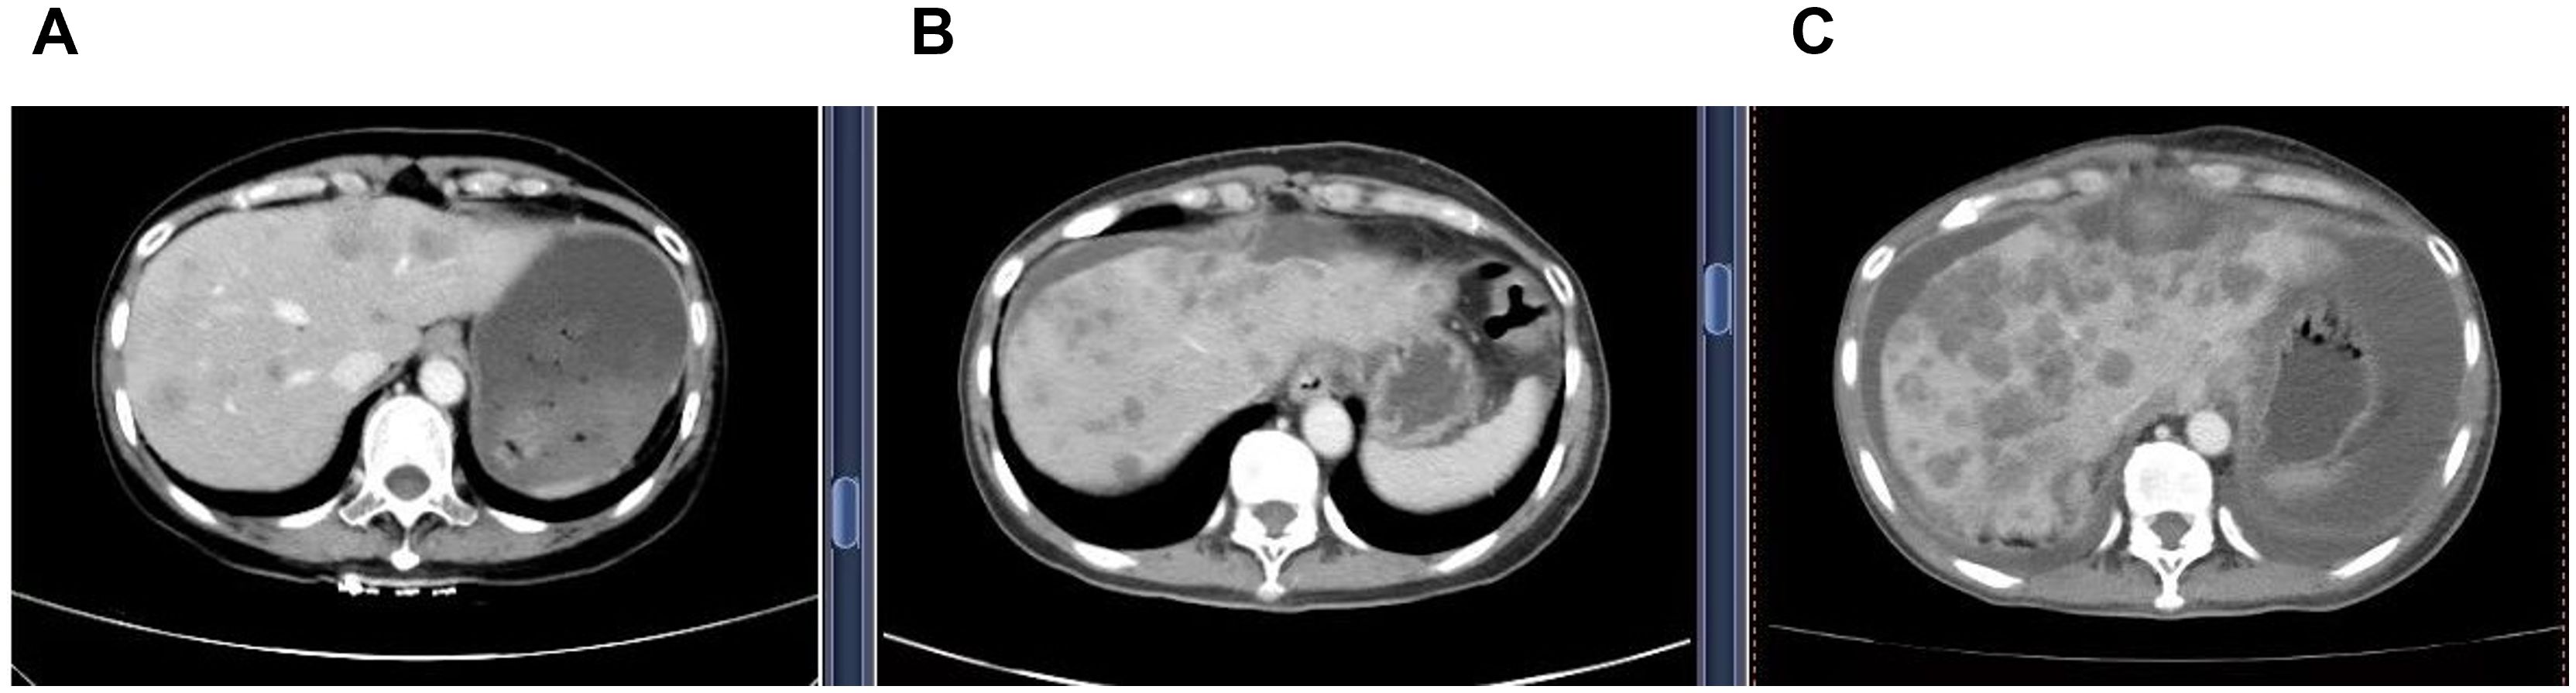

The patient was treated on multiple occasions between April 2023 and November 2024 for progression of liver metastases. The treatment details are summarized in Table 1 and Figure 1.

A series of three abdominal CT scan images (A, B, and C) showing cross-sectional views of the liver at different time points, highlighting the evolution and changes in liver metastases.

Figure 1. Serial contrast-enhanced abdominal CT images demonstrating progression of hepatic metastases. (A) (21 April 2023) Multiple new hypodense liver nodules of varying sizes, the largest measuring 5.0 x 3.6 cm. The lesions demonstrate mild, heterogeneous, enhancement with ill-defined margins. These findings are new compared to the prior examination and are consistent with metastatic disease. (B) (16 July 2024) Increase of low-density hepatic nodules with ill-defined margins, and mild heterogeneous enhancement. The dominant lesion in the quadratic lobe measures 5.7 cm x 4.9 cm, showing peripheral fusion and subcapsular extension, consistent with disease'progression. (C) (22 October 2024) Increase in both size and number of multifocal low-density hepatic nodules, with mild heterogeneous enhancement, ill-defined margins, and areas of confluence. The largest lesion in the left lobe measures 7.1 cm x 4.9 cm. These findings are consistent with progressive metastatic disease.